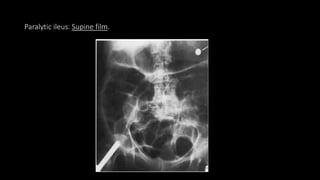

Paralytic ileus

• It occurs when intestinal peristalsis ceases and fluid and gas accumulate in the

bowel loops.

• Postoperative

• Peritonitis

• Inflammation

• Trauma

• Drugs

• CHF , Renal Failure

• Leaking abdominal aortic aneurysm

• Hypokalemia

• General debility or infection

• Vascular occlusion

• Pneumonia

 causes

Paralytic ileus. Supine film.

Paralytic ileus • Itoccurs when intestinal peristalsis ceases and fluid and gas accumulate in the bowel loops. • Postoperative • Peritonitis • Inflammation • Trauma • Drugs • CHF , Renal Failure • Leaking abdominal aortic aneurysm • Hypokalemia • General debility or infection • Vascular occlusion • Pneumonia  causes

• #58 Paralytic ileus. Supine film. There is generalised dilatation of both small and large bowel. An 84-year-old woman with generalised peritonitis following perforation of a gastric ulcer